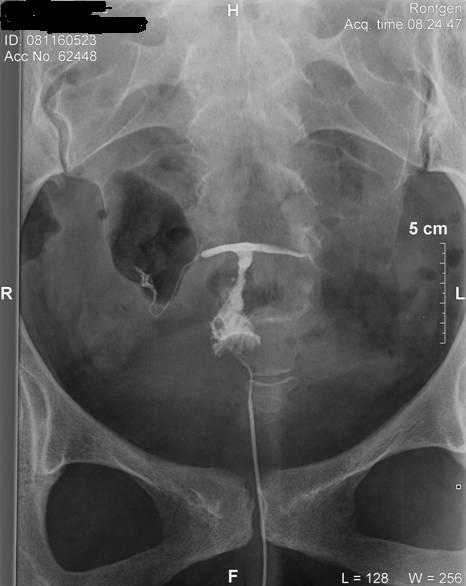

Hát hsg megvolt, nem volt egy rózsaszín leányálom mire felrakta a katéter, mert csak a második katéter ment be a helyére, és sokadik próbálkozásra!!!! :cry: Nem kívánom senkinek!!!!! De túl vagyok rajta, jobb mint a lapar!!!!!! :roll:

Szóval a helyzet az, hogy történt valami odabent, mert rettentő vékonyak lettek a vezetékek, kanyargósak, és a főnököm és az itteni nőgyógyi (aki felrakta a katétert) szerint hegesen gyógyultam régebbi gyulladásból. :cry: Szerinte ne is az inszemivel, hanem a lombikkal próbálkozzunk!!!!! :? :cry: Hát elkenődtem, mert nem erre számítottam, hiszen volt laparom, hsg-m eddig teljesen jó eredménnyel. :( Viszont megyek vissza a dokimhoz majd ha megjön, és megmondja a frankót!!!!! Hát ő azért már több ilyet látott, mint ez a nődoki!!!! :shock:

És a képes bizonyíték!!!!

Kép

én sem tudom, mit kell nézni a fotokon. de én is arra gondoltam, hogy ha kanyargos a petevezetö, akkor ott elakadhat a magzat, emiatt biztonságosabb lenne a lombik. ha babás leszel spontán, neked nem árt meg a röntgensugár? vagy nem közvetlen a sugárban dolghozol???